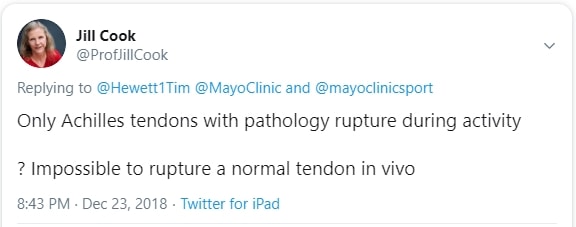

7. 66% от руптурите на ахилесовото сухожилие са безсимптомни(Kannus et al. 1991). Това означава, че тези хора никога не са имали чувствителност, скованост, болка или дисфункция на ахилеса. Въпреки това в сухожилието е трябвало да има някаква патология, тъй като авторите показват, че 98% от разкъсаните сухожилия са имали дегенеративна патология, а 2% - друга патология. Джил Кук обясни това в публикация в Twitter, заявявайки, че е невъзможно да се скъса нормално сухожилие in vivo без патология.